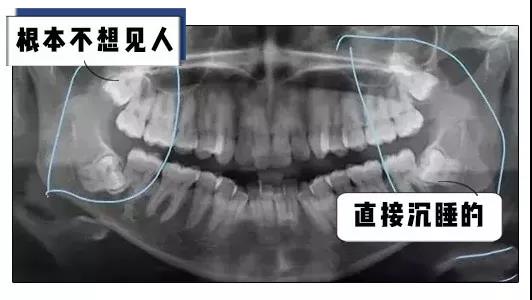

可是一般人的智齿都是这样长的

这样长的

甚至还有这样长的

各种奇形怪状